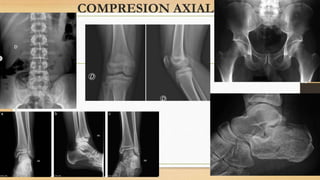

MECANISMO

DE ACCION

Las fracturas de los platillos tibiales pueden

producirse por una gran variedad de fuerzas.

- Valgo y varo forzados

- Compresión axial

- Flexión / Extensión

- Traumatismo directo

COMPRESION AXIAL

MECANISMO DE ACCION Las fracturasde los platillos tibiales pueden producirse por una gran variedad de fuerzas. - Valgo y varo forzados - Compresión axial - Flexión / Extensión - Traumatismo directo Existen dos subgrupos Pacientes jóvenes con buen hueso - alta energía Pacientes ancianos con osteoporosis - baja energía